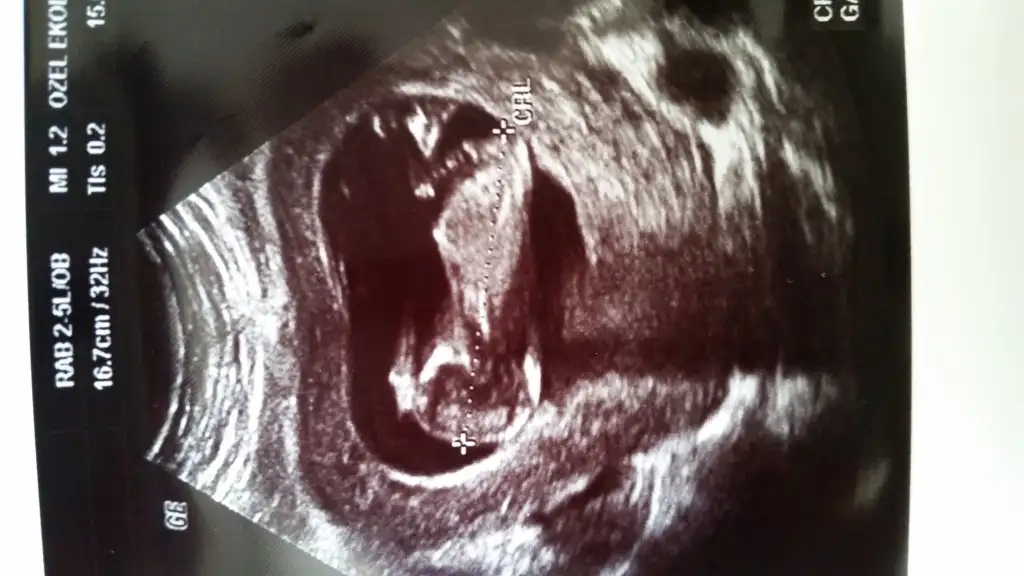

Iste bu bak erkek nub u dik duruyor...insallah oglun olur..bende 3. Yu deneyecemEki Görüntüle 1532537 Canim buda normal ultrasyon resmi simdi belli oluyomu

Canim kesin erkek senin ki ben net gorduklerime yorum yapiyorum..emin olmadiklarima yorum yapmamTeşekkür ederim hayırlısı yorum yapan az oldu pek belli olmuyor galiba

Onden gidiyorsa erkek tir..ilk foto da erkege benzettim..ama ikinci foto paralel gibi geldi...emin olamamakla erkek diyorum..% 60.... bir de cok minik cekilmis bebis..sata gore 11 arti 5 ultrason 12 arti 2 kizlar ne cinsiyeti cevallarsaniz sevinirim.

canim senin ki erkek cunku benim bebegimde ultrasyon da ayni o pozisyondaydi doktor yuzde 70 erkek dedi hayirlisi olsuntekrar koymak istedim merak çok kötü bişey

INSALLAH canim dedigindir doktor demisti erkek yuzde 70 kesinlesirse soylerim INSALLAH senin 3 de erkek olur hayirli si olsun bizler icin:)))))Iste bu bak erkek nub u dik duruyor...insallah oglun olur..bende 3. Yu deneyecem

Onden gidiyorsa erkektir...Allah gonlunuze versin insallahİnş.canım Allahım gönlümüze göre versin,aslında bi çıkıntı var gibi ben istediğim için mi bilmiyorum erkek nubu na benzettim 2. Tefa yüklediğimde daha belli resim canım dediğim gibi 10.haftada gitmiştim dktr.ama bir hafta önden gidiyoruz bilmiyorum etki eder mi nubu ama tabi hayırlısı